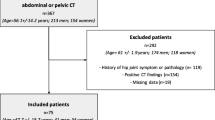

As part of the Norwegian prospective multi-centre study on Perthes’ disease, 425 patients were registered between 1996 and 2000 [8]. We analysed both the affected as well as the unaffected hips in all cases with unilateral involvement, age at onset 6 years or older and femoral head necrosis more than 50 % (n = 152). Radiographs were taken at diagnosis and at 1- and 5-year follow-up. The degree of femoral head necrosis was assessed according to the original Catterall classification [9]. We included radiographs classified as groups III and IV. Twenty-nine children were excluded due to inadequate exposure of the acetabular landmarks. Thus, 123 children (90 boys and 33 girls) with a mean age at the time of diagnosis of 7.5 years (range 6–13 years) were studied.

The radiographic phase was determined at the time of diagnosis according to Waldenström [10]. Sixty-three hips were in the initial phase (51 %), 48 were in the fragmentation phase (39 %), five were in the reossification phase (4 %) and seven hips had not been classified (6 %).

We applied the original lateral pillar classification of Herring et al. [11] in 110 patients at the fragmentation phase. Sixty hips were classified as lateral pillar type B (54.5 %) and 50 hips as lateral pillar type C (45.5 %). The femoral head cover was calculated as the percentage of the femoral head medial to Perkin’s line compared to the width of the femoral head, both measured parallel to Hilgenreiner’s line [4].

The children included in this study received either physiotherapy (n = 55), Scottish Rite orthosis (n = 26) or proximal femoral varus osteotomy (n = 71) [8], according to the choice of the local orthopaedic surgeons. The decision was based on surgeons’ preferences, treatment philosophy and local tradition. We combined patients treated with physiotherapy and orthosis into a non-operative treatment group.